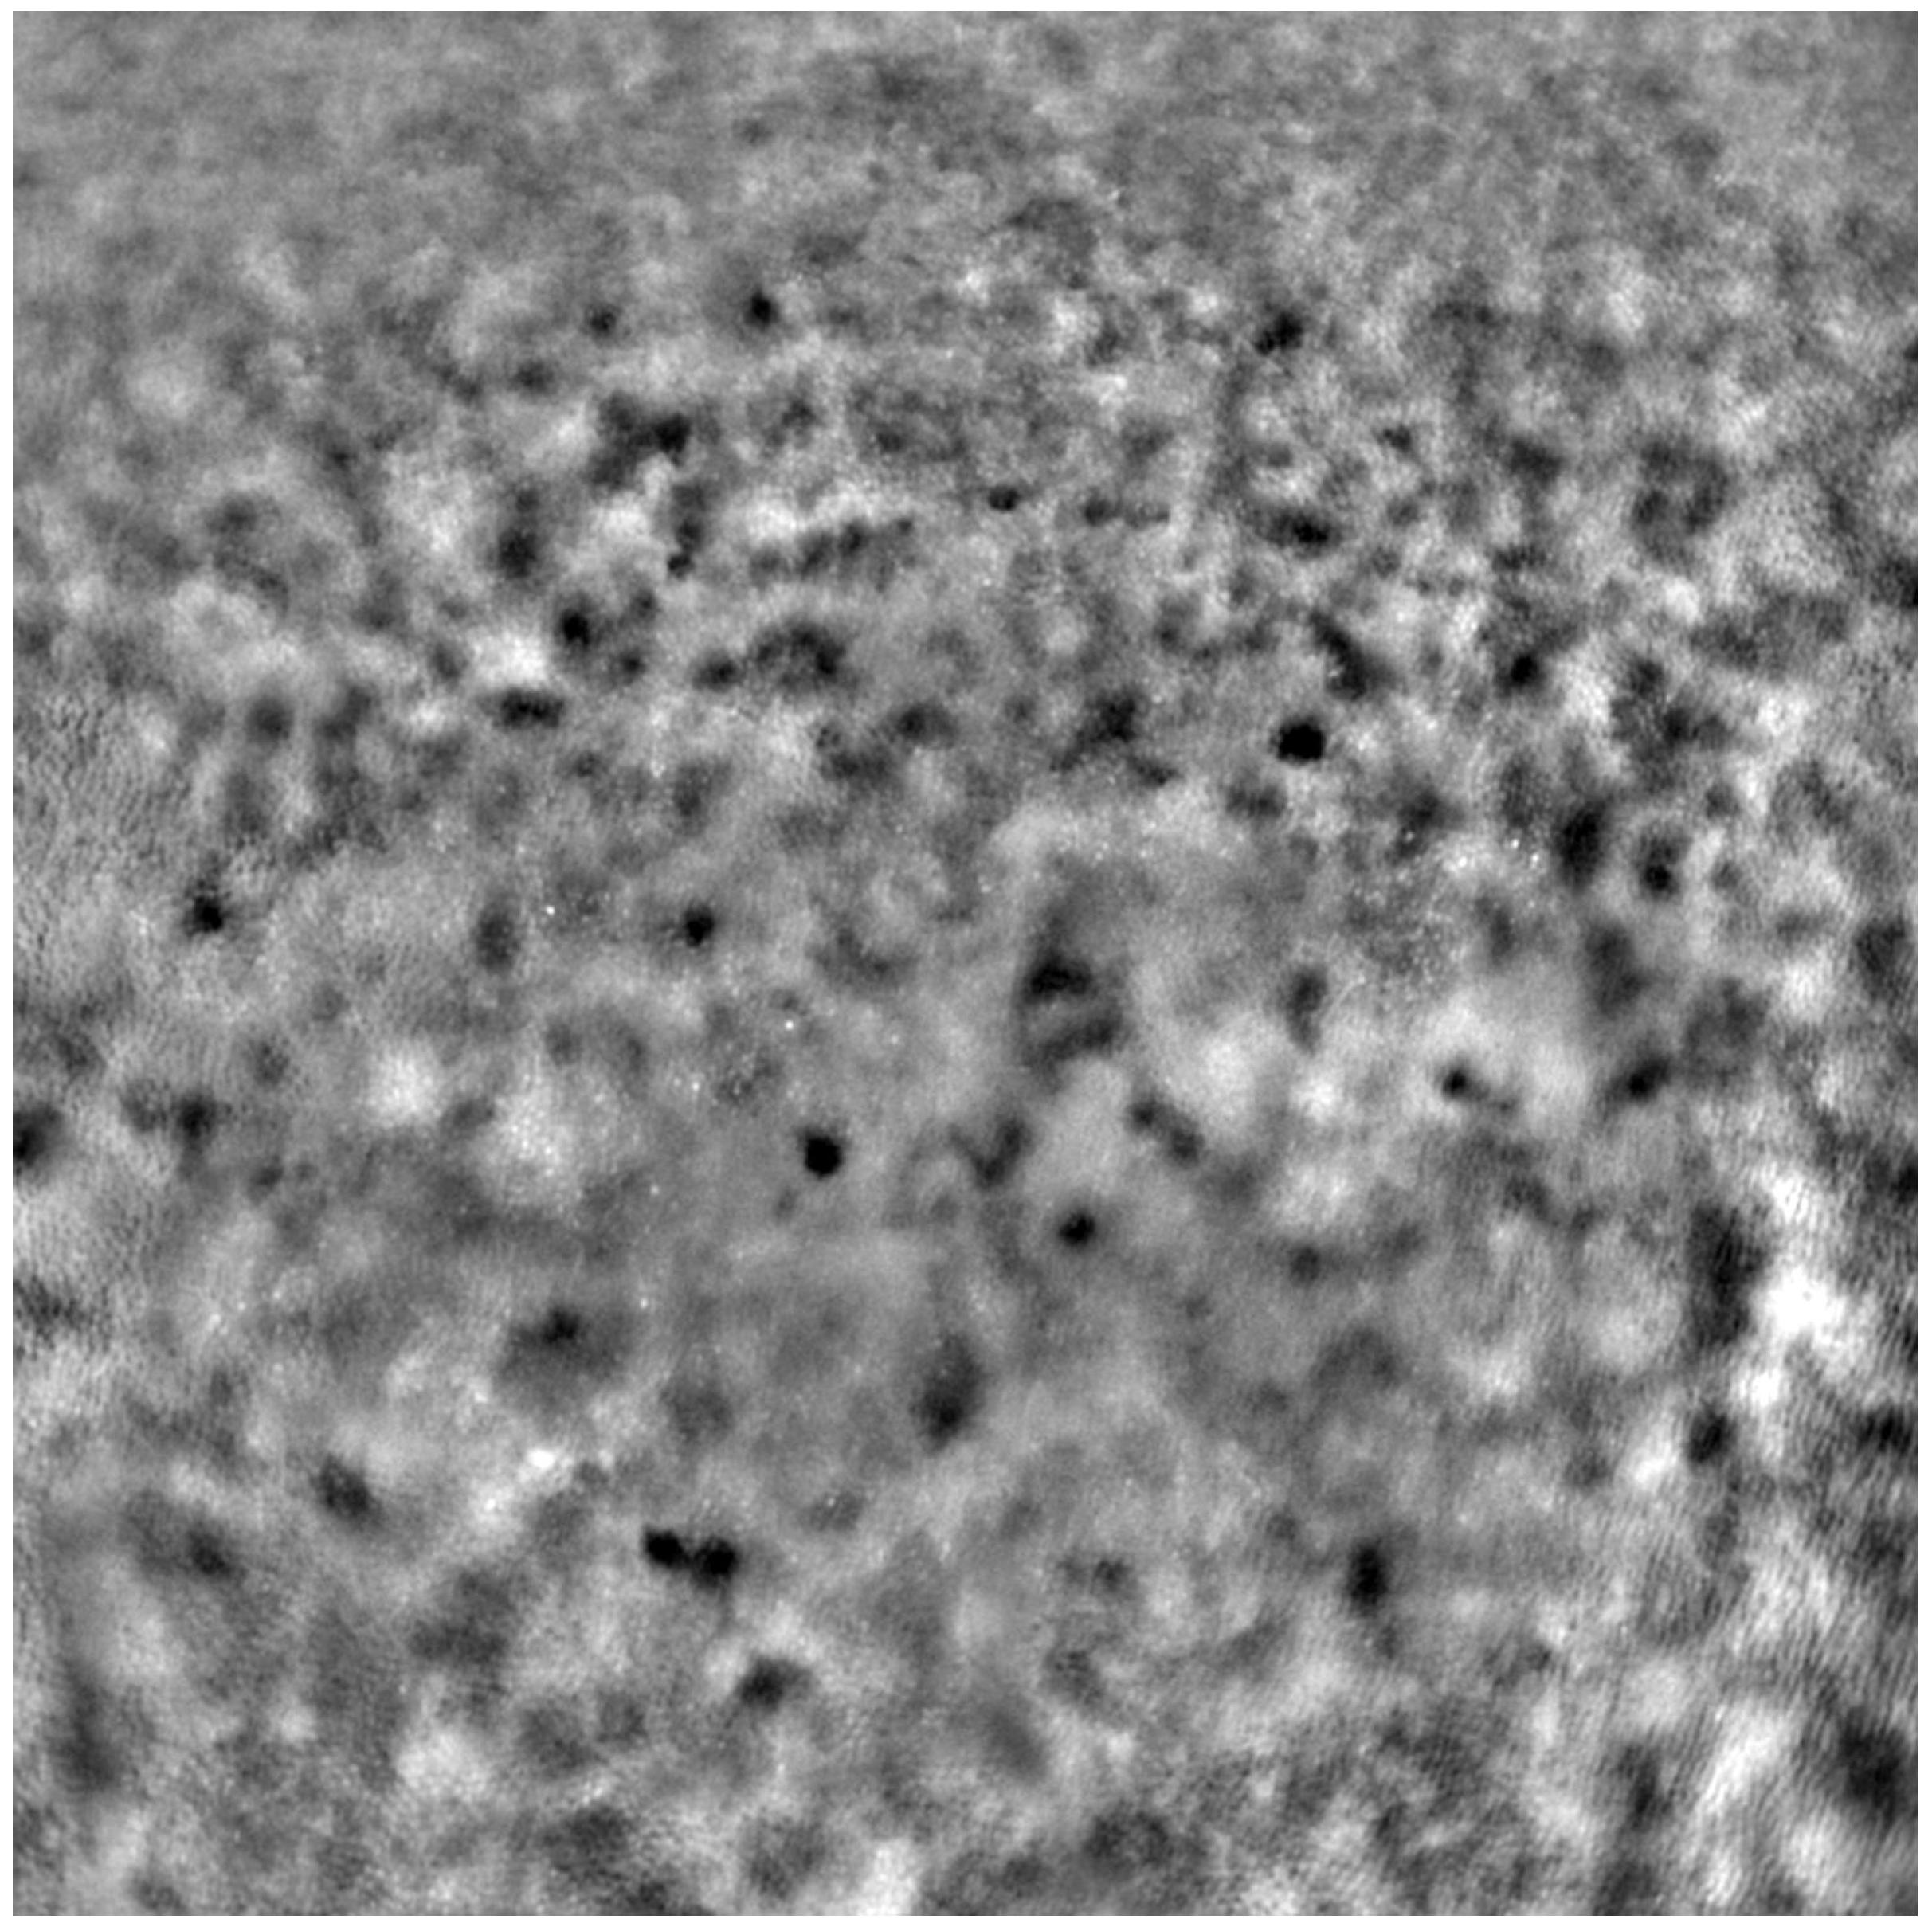

Adaptive optics retinal images depicting a healthy eye, CD, CRD, and STGD are presented in Figure 1, Figure 2, Figure 3 and Figure 4.

Figure 1 depicts the photoreceptor mosaic in a healthy eye. The image is taken paracentrally (2 ° superiorly) due to the limited ability of foveal image acquisition by Rtx™ [17]. By changing the focus point, the quality of an acquired image provides the assessment of photoreceptor parameters in parafoveal cones. The aberration and noise found in Figure 2, Figure 3 and Figure 4 are considered to be the result of poor fixation in eyes with impaired central vision in the course of macular disease. This issue has been addressed in our study. The assessment of factors predisposing for obtaining inadequate image quality was taken into consideration further in this article.

Figure 1. An adaptive optics image showing photoreceptors in a healthy eye (Rtx1™, Imagine Eyes, France). The photoreceptor mosaic appears intact (not disrupted) with individual photoreceptors visible as white and greyish spots.